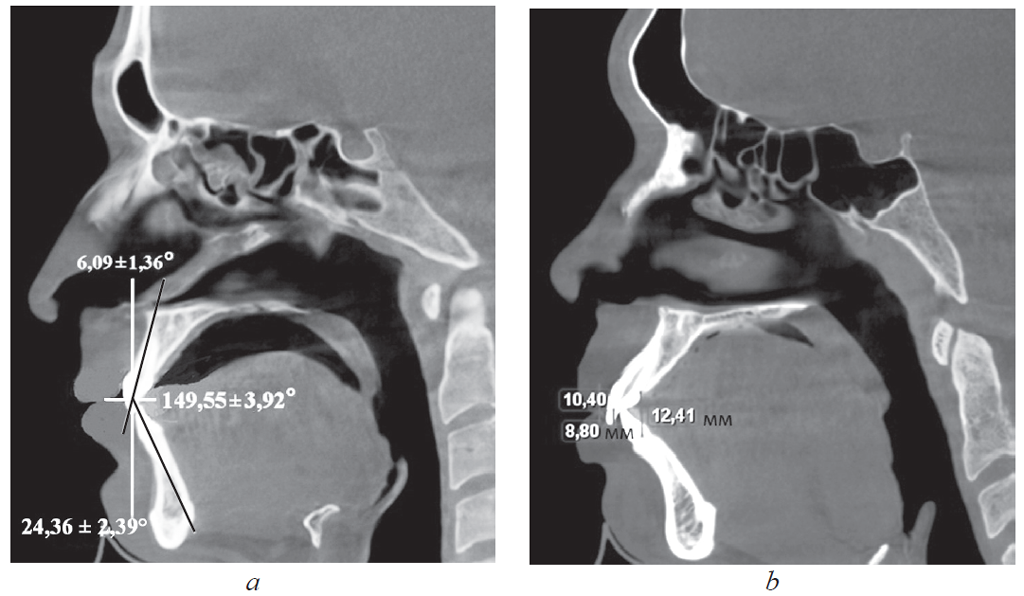

Results. People with Group 1 protrusion incisors angle was 149.55 ± 3.92°. Tork upper incisors were 24.36 ± 2.39° degrees. When retrusion incisors angle was 151.47 ± 2.94°, tork upper incisors was 5.85 ± 1.42°. In this case, the vertical overlap is in the sagittal and 2-3 mm is not exceeded. Group 2 patients, as a rule, noted the violation of form dental arches in the anterior segment.

У людей 1-й подгруппы, для которых было характерно протрузионное положение резцов, межрезцовый угол составил 117,24 ± 2,85°. При этом торковые значения верхних резцов по отношению к окклюзионной плоскости составили 12,24 ± 2,48° (рис. 2).

Рис. 2. Физиологическая протрузия резцов на томограммах

Fig. 2. Physiological protrusion of incisors on tomograms

У людей 2-й подгруппы при ретрузии резцов величина межрезцового угла в среднем составила 151,47 ± 2,94°, торк верхних резцов — 5,85 ± 1,42°. При этом величина вертикального перекрытия соответствовала величине сагиттального перекрытия и не превышала 2–3 мм.

У людей 1-й подгруппы, для которых было характерно протрузионное положение резцов, межрезцовый угол составил 117,24 ± 2,85°, при этом торковые значения верхних резцов по отношению к окклюзионной плоскости — 12,24 ± 2,48° (рис. 4).

Рис. 4. Патологическая ретрузия (а) и патологическая протрузия (b)

Fig. 4. Pathological retrusion (a) and pathological protrusion (b)

У пациентов с ретрузией резцов отмечалось увеличение межрезцового угла и уменьшение торковых значений резцов, так же как и при физиологической ретрузии. Однако величина перекрытия существенно отличалась от аналогичных показателей, полученных у пациентов I группы. При этом наблюдалось несоответствие размеров вертикального и сагиттального перекрытия.